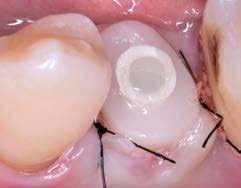

A behelyeztt implantátum primer stabilitását megfelelőnek ítéltük (kb. 40 Ncm) az azonnali terheléshez (9. kép).

Az extrakciót megelőző szituációs lenyomat alapján gyári, titán, ideiglenes abutment felhasználásával, a szék mellett készített, csavaros rögzítésű, azonnali akrilát ideiglenes koronával láttuk el, melyet 20 Ncm nyomatékkal rögzítettünk (10. kép). Az azonnali terhelés szabályainak megfelelően, az ideiglenes korona nem volt kontaktusban a szomszédos és az antagonista fogakkal.